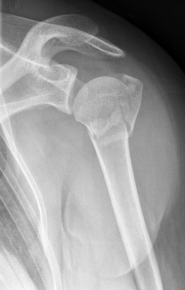

Proximal Humeral Fracture

The proximal or shoulder-joint humeral fracture accounts for 5% of all fractures and is a typical fracture of the elderly. Often it is associated with osteoporotic bone changes, so that even a small trauma leads to breakage. It occurs in younger patients, usually as a result of a high speed impact injuires.

The most common form is the subcapital humeral fracture just below the humeral head, but also the humeral head can be directly affected.

Proximaler Oberarmbruch9Proximaler Oberarmbruch10

Picture: A subcapital upper arm fracture was treated with a prosthesis. The humeral head was completely removed and replaced by the prosthesis. This is anchored in the upper arm with the prosthesis shaft.